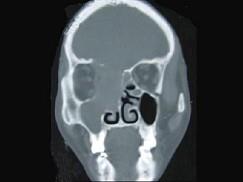

问题 女性,53岁,右侧鼻腔流血近一年,近来头痛,行CT检查如图所示,请选择正确的答案 ( )

选项 A、鼻腔炎性假瘤 B、鼻腔内血管瘤 C、鼻腔内息肉 D、副鼻窦炎 E、鼻腔癌

答案 E